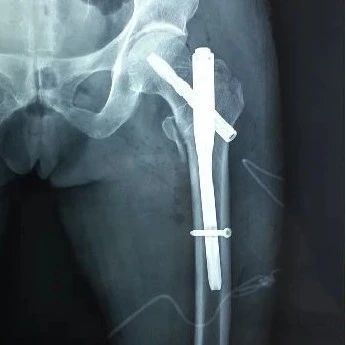

股骨转子间骨折“隐性失血”为哪般?

股骨转子间骨折围手术期隐性失血的研究进展

随着我国人口老龄化的加剧,股骨转子间骨折的发病率逐年上升。因保守治疗需要长期卧床制动,并发症较多,严重影响患者的生存率,目前多主张手术治疗。Pattison等最初在行全膝关节置换术时发现患者术后血红蛋白(Hb)下降程度与术中失血量严重不符的情况,并推测除了术中可见出血外,还存在着大量的不可见失血。